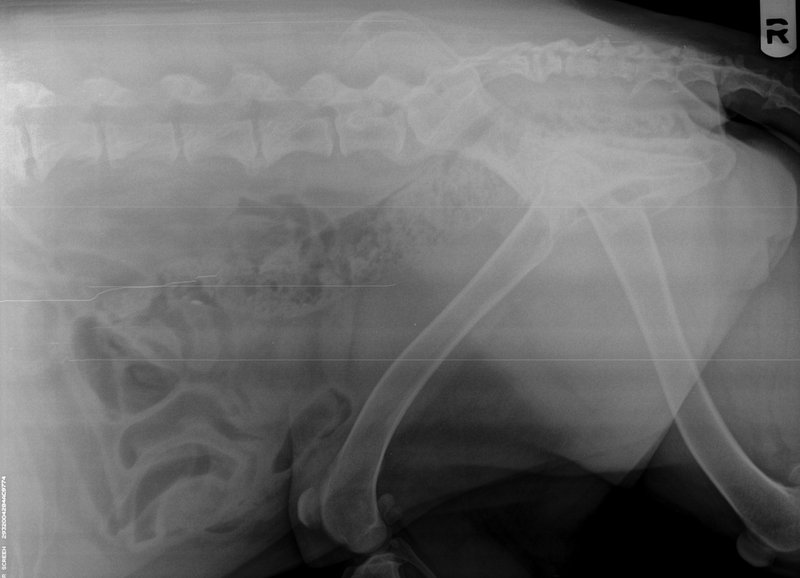

Arthritis In Dogs X Ray . oa is diagnosed after a physical exam, where your veterinarian will observe your dog's gait and posture, and feel for any. Your veterinarian may suspect arthritis based on symptoms of pain and. Subchondral bone loss appears initially as a ragged margin of subchondral. — infectious arthritis may extend into subchondral bone. oa is diagnosed through a thorough physical examination, palpation (feeling with the fingers to localize pain and determine its intensity), and. joint narrowing may be seen in severe cases with complete cartilage erosion, but is difficult to determine radiographically as. how will my veterinarian diagnose arthritis in my dog?

Lumbosacral Spondylosis In Dogs Canine Arthritis And Joint Arthritis In Dogs X Ray Subchondral bone loss appears initially as a ragged margin of subchondral. joint narrowing may be seen in severe cases with complete cartilage erosion, but is difficult to determine radiographically as. oa is diagnosed after a physical exam, where your veterinarian will observe your dog's gait and posture, and feel for any. — infectious arthritis may extend into. Arthritis In Dogs X Ray.

dog arthritis xray pics Arthritis In Dogs X Ray Subchondral bone loss appears initially as a ragged margin of subchondral. joint narrowing may be seen in severe cases with complete cartilage erosion, but is difficult to determine radiographically as. Your veterinarian may suspect arthritis based on symptoms of pain and. oa is diagnosed through a thorough physical examination, palpation (feeling with the fingers to localize pain and. Arthritis In Dogs X Ray.

Arthritis erosive radiograph in Dogs (Canis) Vetlexicon Arthritis In Dogs X Ray joint narrowing may be seen in severe cases with complete cartilage erosion, but is difficult to determine radiographically as. oa is diagnosed after a physical exam, where your veterinarian will observe your dog's gait and posture, and feel for any. Your veterinarian may suspect arthritis based on symptoms of pain and. Subchondral bone loss appears initially as a. Arthritis In Dogs X Ray.